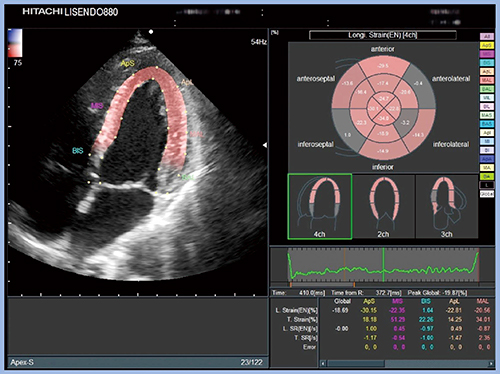

HFpEF(LVEFが保たれた心不全)については従来,高血圧フェノタイプやDMフェノタイプなどに分けてリスクへの介入を行ってきたが,近年はエコーで分類することが提言されている5)。具体的には,まず心不全をHFpEFかHFrEF(LVEFが低下した心不全)かで分類し,次にGlobal Longitudinal Strain(GLS)が保たれているかどうかで分類する。GLSが低値の場合は心筋の線維化や過度の左室肥大反応,蓄積性心疾患(心アミロイドーシス)が考えられるため,cardiac phenotypeに分類する。一方,GLSが保たれている場合は血管不全や後負荷不整合が考えられるため,vascular phenotypeに分類し,血管や心臓だけでなく全身を診ていこうというものである。

日立製の超音波診断装置「LISENDO 880」では,“2D Tissue Tracking”にて2Dスペックルトラッキングの解析が可能であり,GLSがきわめて良好に算出される(図3)。2D Tissue TrackingではLVEFも併せて表示されるため,心不全症例のLVEFやGLSの分類は本機能のみで行うことができる。

図3 2D Tissue TrackingによるGLSの算出